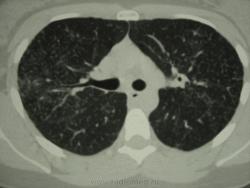

девушка 1985 г.р. дообследована после профилактической флюорографии, на КТ написали гистиоцитоз. Диагноз пока не подтвержден. Жалоб не предъявляет, курит в течение 8-9 лет. консультирована у фтизиатров, свою патологию они исключили.

Но, КТ, по всей видимости, свидетельствует, именно, о диффузности процесса, с некоторым превалированием в отдельных отделах.

Изменения диффузны. По rg более выраженны в нижних отделах, за счет марсива тканей. Ждем анализ мокроты и промывных вод.

И, хотя, по КТ, был выставлен гистиоцитоз, в первую очередь должен быть исключен или подтвержден "Его величество туберкулёз".

Очень на то похоже, что аналогия..."Более 90% больных гистиоциозом-Х (Лангергасоклеточным гистиоцитозом) - курильщики"...